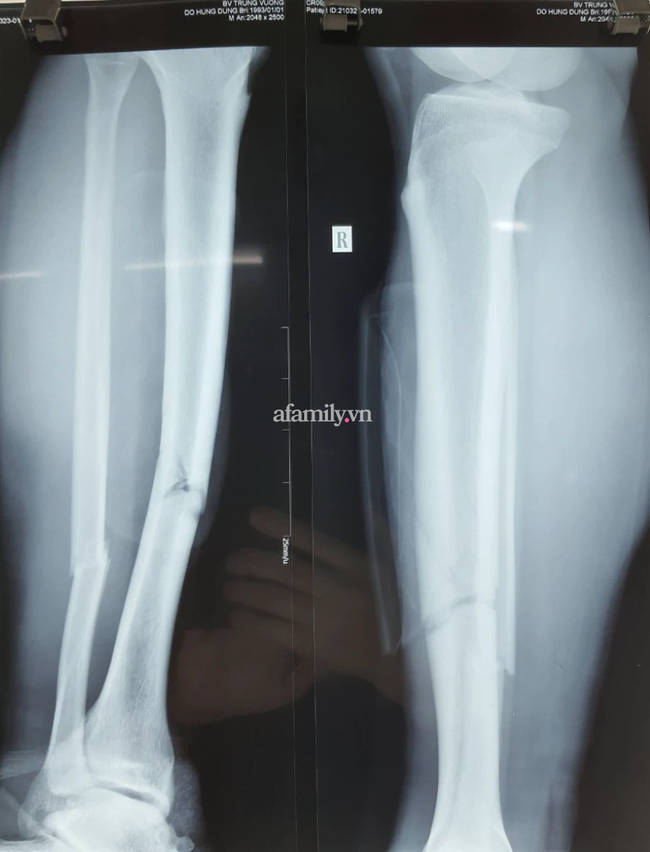

Đến trưa 24/3, đại diện Bệnh viện (BV) Vạn Hạnh (TP.HCM) cho biết, ca phẫu thuật kết hợp xương cho cầu thủ bóng đá Đỗ Hùng Dũng đã bước đầu thành công.

Cụ thể thành viên trong ekip mổ cho biết, bệnh nhân được phẫu thuật bằng phương pháp đóng đinh nội tuỷ xương chày trên màng hình tăng sáng (C-arm). Ca mổ hoàn toàn thuận lợi, bắt đầu lúc 9h và kết thúc lúc 10h30 cùng ngày.

Dự trên hình ảnh phim, tình trạng gãy xương của bệnh nhân không phức tạp, không di lệch nhiều, không có nhiều mảnh vỡ.

Dù vậy với một cầu thủ bóng đá, việc trở lại như bình thường rất khó vì việc gãy ít nhiều ảnh hưởng đến xương. Nhưng hi vọng với tổn thương như hiện tại cũng như kỹ thuật mổ tốt, chăm sóc tận tình có thể giúp bệnh nhân có tiến triển tốt đẹp" - phẫu thuật viên chính chia sẻ.

Trong khi đó, chấn thương của cầu thủ Hùng Dũng nằm ở xương, không liên quan đến dây chằng. Các bác sĩ hi vọng nếu hồi phục thuận lợi và có ý chí tốt, Đỗ Hùng Dũng có thể trở lại tập luyện trong 5-6 tháng. Phong độ của cầu thủ này sau chấn thương cũng phụ thuộc vào việc kiên trì tập luyện.

Sau khi tiến hành điều trị giảm đau, kết quả chụp X-quang cho thấy bệnh nhân bị gãy xương mác và xương chày ở 1/3 giữa dưới cẳng chân khá nghiêm trọng.

Dù vậy bác sĩ nhận định vị trí gãy ít di lệch, không bị dập nát, không vỡ xương phức tạp. Đây là điều may mắn cho nam tuyển thủ quốc gia trước cuộc mổ.